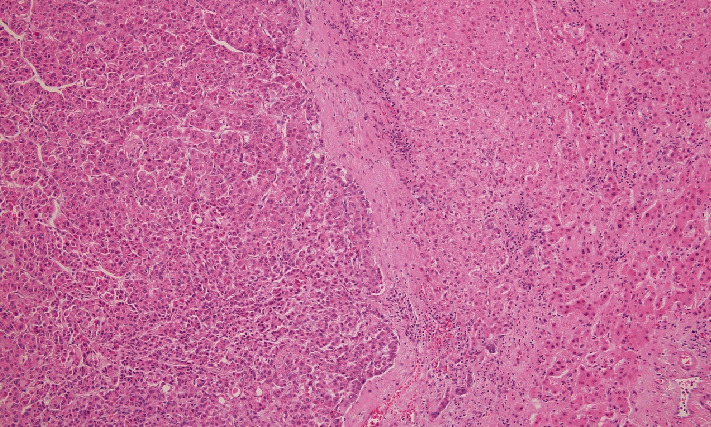

Prostate-specific membrane antigen positron emission tomography (PSMA PET) has been approved by the Food and Drug Administration (FDA) to identify prostate cancer in the setting of biochemical recurrence but can also identify other malignancies. 18F-PSMA PET has not been studied as a potential tool for hepatocellular carcinoma (HCC). We describe the case of a 76-year-old male with a rising prostate-specific antigen (PSA) after definitive prostate cancer treatment and no prior liver pathology who was incidentally found to have HCC on 18F-PSMA PET.

Abstract Image